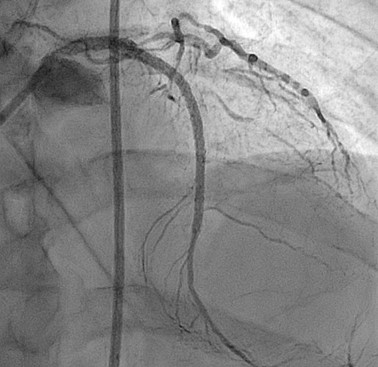

We report an 62-year-old gentleman with history of hypertension, diabetes mellitus, dyslipidemia and history of PTCA to LAD and RCA with DES in 1997. He underwent a computed tomography coronary angiography (CTCA) examination for stable angina which revealed severe in stent restenosis with multiple calcified plaques. Guideline directed medical therapies were optimized. After family conference for mode of revascularization, committed to high-risk percutaneous coronary intervention (PCI) approach.

Contralateral injection approach PCI. Difficulty in wiring occluded LAD segment with Fielder XT-A and Gaia Next 2nd despite with Corsair Pro XS support. Wiring of LAD was successful after escalation to Gaia Next 3rd. After failed attempts to deliver microcatheter, 0.9mm excimer coronary laser atherectomy (ELCA) was performed for 12 cycles (60/80, blood medium) followed by predilatation with Sapphire 3 0.85/10 and Sapphire 1.5/10. Delivery of the microcatheter over the lesion was then successful. Gaia Next 3rd wire then exchanged to NS Runthrough. Predilatation of the lesion with NC Sapphire 2.0/15 and NC Trek 2.5/15, however noted balloon severe underexpansion. Optical Coherent Tomography (OCT) performed with Dragonfly Opstar showed severely calcified neoatherosclerosis. Four runs of 1.5mm burr rotational atherectomy was then performed at 180,000rpm, followed by another three runs of 1.75mm burr rotablation at 180,000rpm. We then deployed DES Xcience Skypoint 2.5/38 to m-dLAD and another DES 3.5/28 Xcience Skypoint to the LM-pLAD region due to dissection flap evident in OCT. Lesion segment between DES was subsequently prepared with intravascular lithotripsy (IVL) 3.0/12 for 80 shocks and NC Pantera Leo 3.0/15 before deploying Xcience Skypoint 3.0/15. DES optimization was then performed under OCT guidance. Finally, DCB 3.0/20 Sequent Please Neo DCB was deployed to mLAD ISR for 60 seconds. Staged PCI to RCA was performed with IVL followed by DES deployment under imaging guidance.